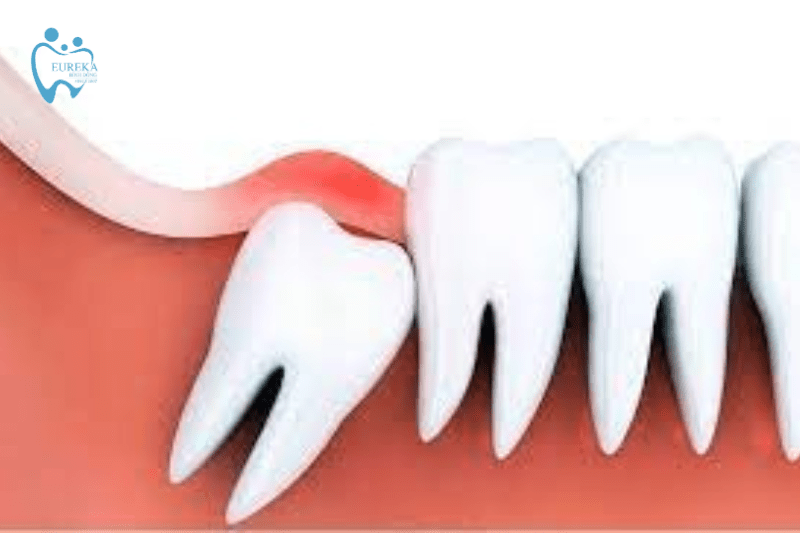

- Viêm lợi do hướng mọc răng khôn

Vì mọc sau cùng và vị trí trong cùng của hàm nên răng khôn không thể mọc đúng hướng như những răng khác. Chúng sẽ mọc nghiêng, ngang, đâm vào răng số 7, thậm chí là mọc ngầm dưới lợi. Từ đó khiến cho phần nướu bị sưng lên và khó được làm sạch, tạo điều kiện cho vi khuẩn phát triển. Lúc này lợi sẽ bị nhiễm trùng, đau nhức và trùm lên răng khôn.